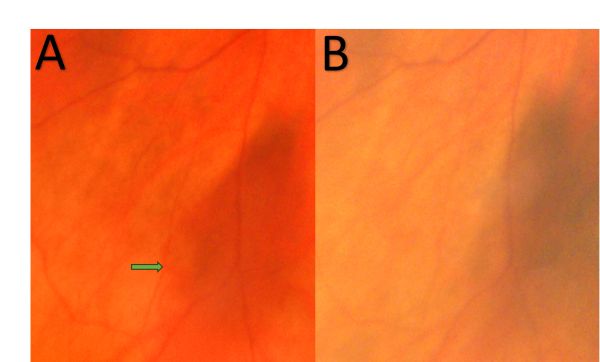

OA OB Figure 1 0 Choroidal vortex varix. (A) Varix fully filled and ...

Fundus photograph of the left eye at initial presentation ...